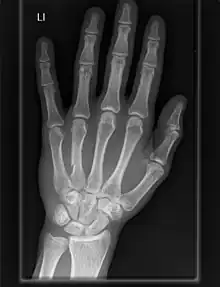

X-ray of a human hand